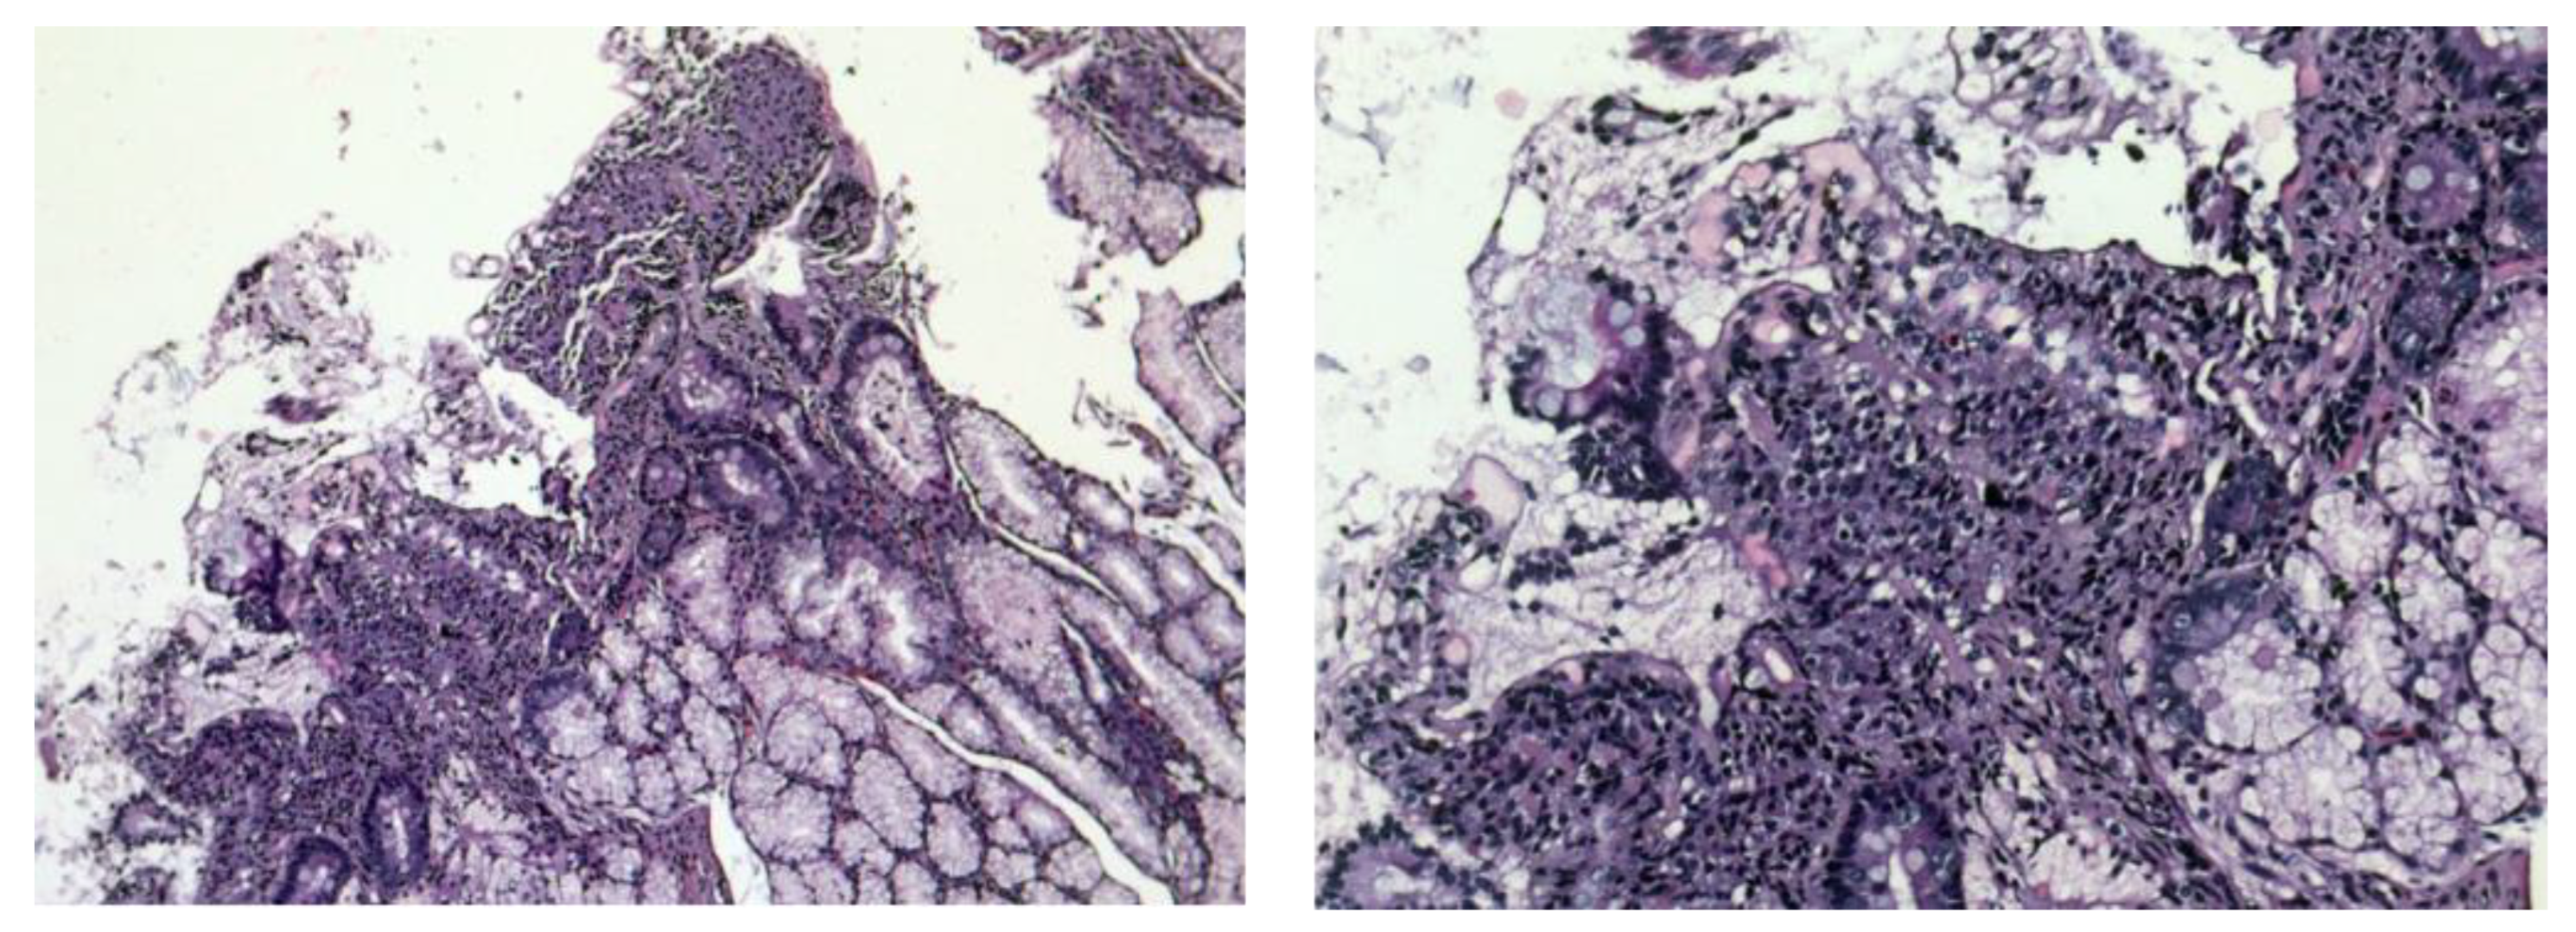

4. Pathophysiology of Villous Atrophy in Gluten Enteropathy